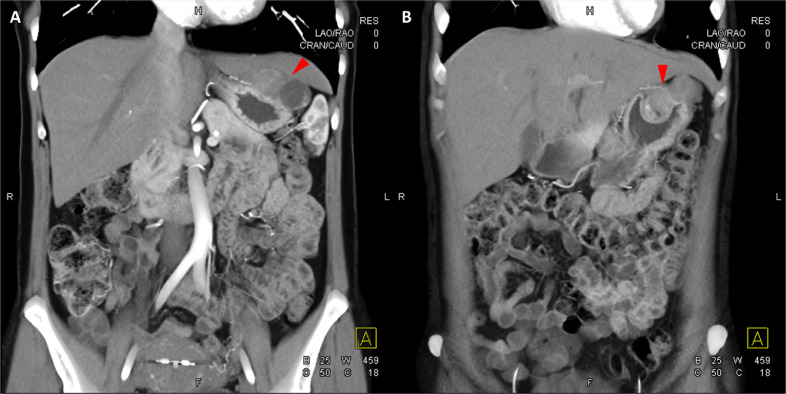

胸部、腹部和骨盆的對比增強動脈和靜脈期 CT 顯示多個圓形、主要是血管豐富的異質腫塊,具有囊性和實性成分,起源于胃底和胃體(圖 2-4)。 病變部分呈外生結構,被認為位于粘膜下層。 在頸部多發(fā)同步性副神經節(jié)瘤的情況下,賊初的鑒別診斷包括多發(fā)性副神經節(jié)瘤、多發(fā)性 GIST 以及轉移性疾病。

圖 3:多個胃腸道間質瘤的冠狀和矢狀圖像。 (A 和 B)冠狀動脈相對比增強 CT 圖像顯示胃賁門產生的外生性腫塊。 (C 和 D)矢狀動脈相位對比增強圖像顯示腫塊的異質性和外生結構。